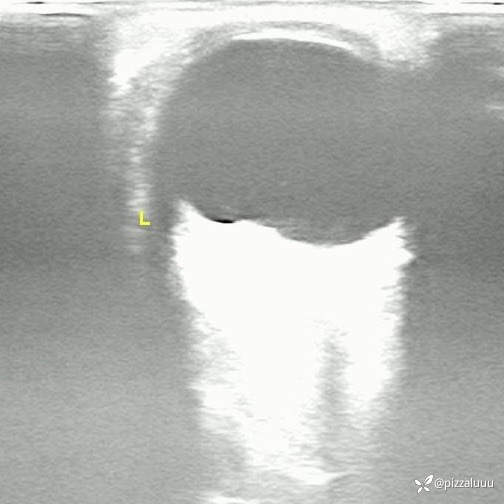

左眼轻度外斜,各位老师考虑这是什么病变?今天只做了这两项检查

玻璃体清,后极部球壁局限隆起,表面粗糙,其内回声不均